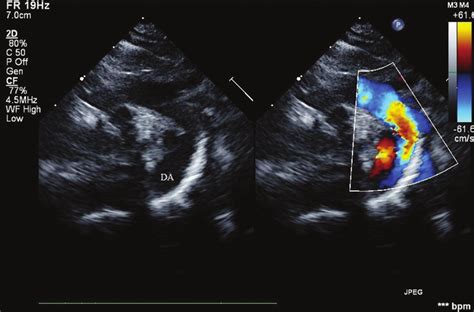

So, how do doctors actually diagnose aorta elongation and aorta calcification ? Since, as we've discussed, these conditions often don't scream for attention with obvious symptoms, diagnostic tools play a vital role. The most common way these are identified is through various **imaging techniques**. An **echocardiogram**, often called an ultrasound of the heart, can provide detailed images of the aorta as it leaves the heart. It can show its size, shape, and how well it's functioning, helping to identify elongation and sometimes signs of thickening or calcification. **Computed Tomography (CT) scans** are also very effective. A CT scan uses X-rays to create cross-sectional images of the body, providing a much more detailed view of the entire aorta. It's excellent at visualizing calcification within the aortic walls and precisely measuring any elongation or dilation. **Magnetic Resonance Imaging (MRI)** is another powerful tool. Similar to CT scans, MRIs use magnetic fields to create detailed images. They can assess the aorta's structure, measure its dimensions, and evaluate blood flow, often without the use of ionizing radiation. For assessing calcification specifically, **coronary artery calcium scoring**, often done with a low-dose CT scan, can quantify the amount of calcium in the coronary arteries, and the scan can also pick up significant calcification in the aorta. Sometimes, calcification might be noted incidentally on a routine chest X-ray, prompting further investigation. Doctors will also consider your **medical history** and **risk factors**. If you have high blood pressure, high cholesterol, diabetes, a history of smoking, or a family history of heart disease, your doctor will be more vigilant in looking for signs of vascular changes. A thorough **physical examination**, including listening to your heart and blood vessels with a stethoscope, might reveal abnormal sounds that could suggest issues with blood flow. Ultimately, diagnosis is usually a combination of imaging findings, patient history, and physical assessment, aiming to get a comprehensive picture of your cardiovascular health.